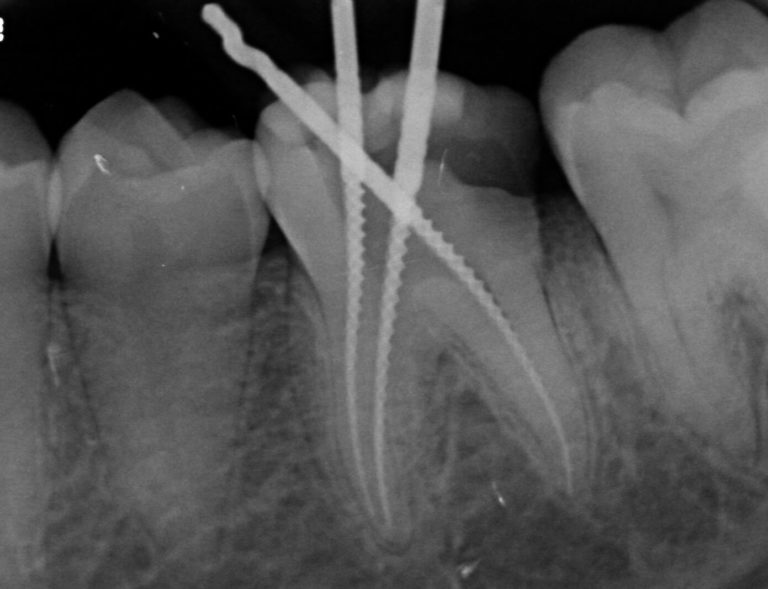

Endodoncia Mal Hecha Quien Paga, Pacientes mal tratados, 20.6 MB, 15:00, 7,693, Dentisto TV, 2018-12-01T20:41:08.000000Z, 3, Síntomas de una endodoncia mal hecha - Clínica Larrañaga, www.clinicadentallarranaga.com, 803 x 620, jpeg, WebUna endodoncia mal hecha puede causar infección y dolor. Así, ¿Que puede salir mal en una endodoncia? A continuación te explicamos que puede salir mal en una endodoncia:., 20, endodoncia-mal-hecha-quien-paga, Novedades y Muebles WebUna endodoncia mal hecha puede causar infección y dolor. Así, ¿Que puede salir mal en una endodoncia? A continuación te explicamos que puede salir mal en una endodoncia:.

WebLa endodoncia es un procedimiento odontológico común con una tasa de éxito muy alta. Sin embargo, hay casos raros en los que un diente tratado no cicatriza. WebLlama la atención, que siendo aún un bajo porcentaje, reciban más del 70% de las reclamaciones (10 reclamaciones por centro al año). Esto se debe a que en este. WebLas etapas de una endodoncia son: Radiografías para revisar el estado del diente afectado y su anatomía. Anestesia local de la pieza. Aislamiento dental. Perforación de la corona.